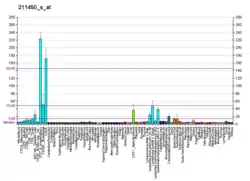

Two microRNAs, miR21 and miR-155, target the DNA mismatch repair (MMR) genes hMSH6 and hMSH2, to cause reduced expression of their proteins.[12][13] If one or the other of these two microRNAs is over-expressed, hMSH2 and hMSH6 proteins are under-expressed, resulting in reduced DNA mismatch repair and increased microsatellite instability.

One of these microRNAs, miR21, is regulated by the epigenetic methylation state of the CpG islands in one or the other of its two promoter regions.[14] Hypomethylation of its promoter region is associated with increased expression of an miRNA.[15] High expression of a microRNA causes repression of its target genes (see microRNA silencing of genes). In 66% to 90% of colon cancers, miR-21 was over-expressed,[12] and generally the measured level of hMSH2 was decreased (and hMSH6 is unstable without hMSH2[13]).

The other microRNA, miR-155, is regulated both by epigenetic methylation of the CpG islands in its promoter region[16] and by epigenetic acetylation of histones H2A and H3 at the miR-155 promoter (where acetylation increases transcription).[17] Measured by two different methods, miR-155 was over-expressed in sporadic colorectal cancers by either 22% or 50%.[13] When miR-155 was elevated, hMSH2 was under-expressed in 44% to 67% of the same tissues (and hMSH6 is likely under-expressed as well, and also unstable in the absence of hMSH2).[13]